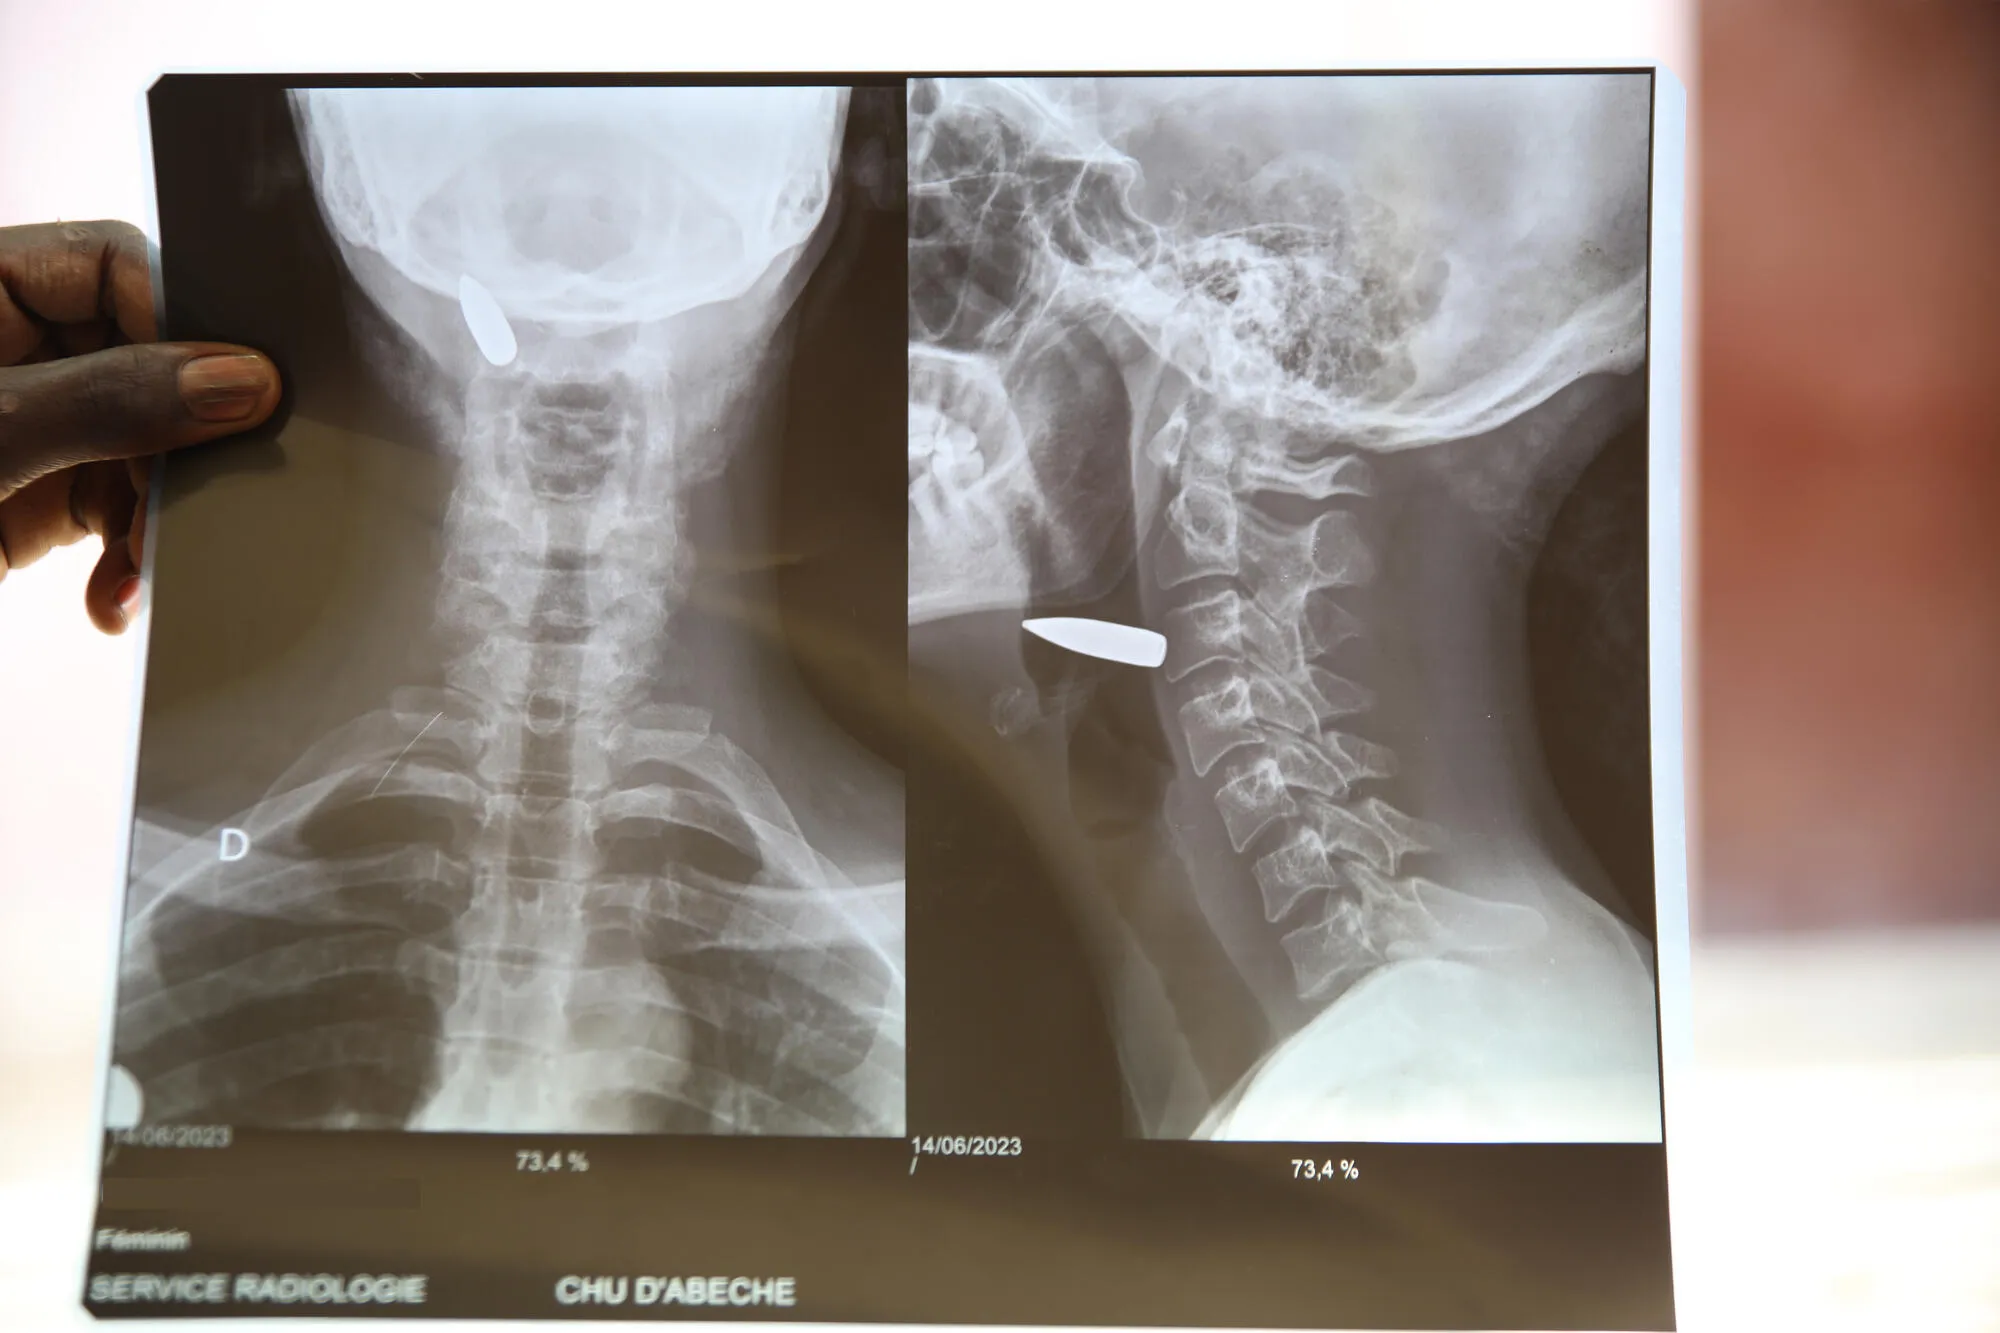

Die Geschichten in den folgenden Bildern erzählen nicht nur von der unermüdlichen Arbeit unserer Mitarbeiter:innen, sondern auch von der Widerstandsfähigkeit unserer Patient:innen, die unter schwierigen Bedingungen um ihr Leben kämpfen und nicht aufgeben.